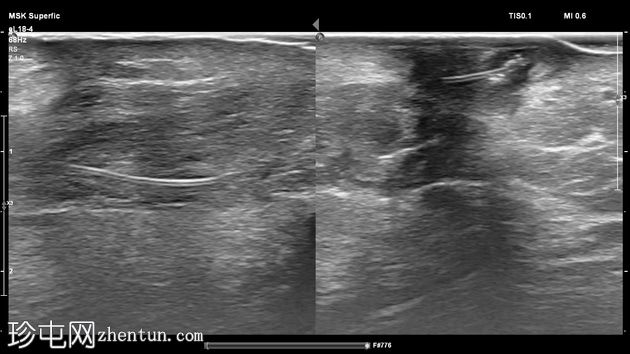

超声检查

4.jpg

横位

左足跟皮下组织内可见一管状高回声物质,呈串珠状,与手术缝线相符,周围环绕着低回声积液。与缝线相连的是一根细细的、呈轨道状的高回声合成单丝,它穿过跟腱呈弧形走行,该缝线为不可吸收缝线。